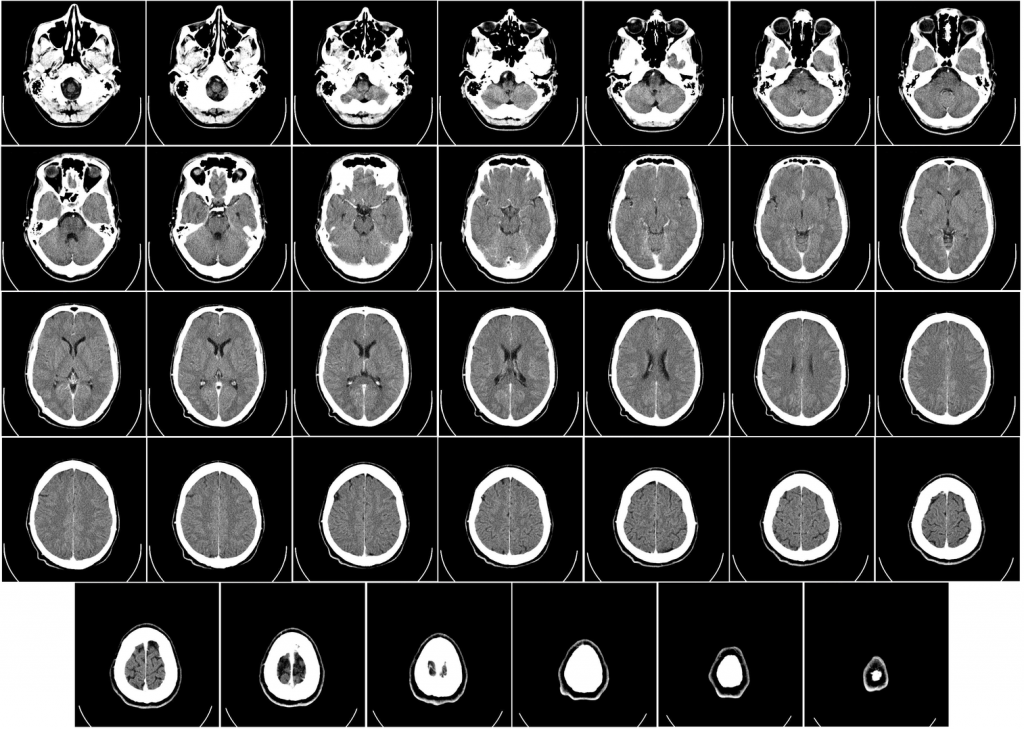

Computed tomography of human brain

Image: CT scan of a human brain (nothing strange was found). Image credit: Department of Radiology, Uppsala University Hospital. Uploaded by Mikael Häggström to Wikimedia. Article by Karla Kaun. The Conversation – January 22, 2024.